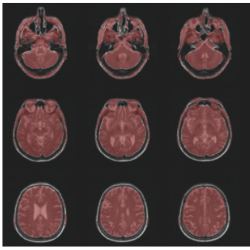

BraTS2020: Since all of the images had already been registered to the same template with size (240, 240, 155), there is no need to apply any registering method for this dataset. The middle axial slices of 4 contrasts are shown in Fig.

9.

Fig. 9

Illustration of axial slices of the BraTS2020 dataset.